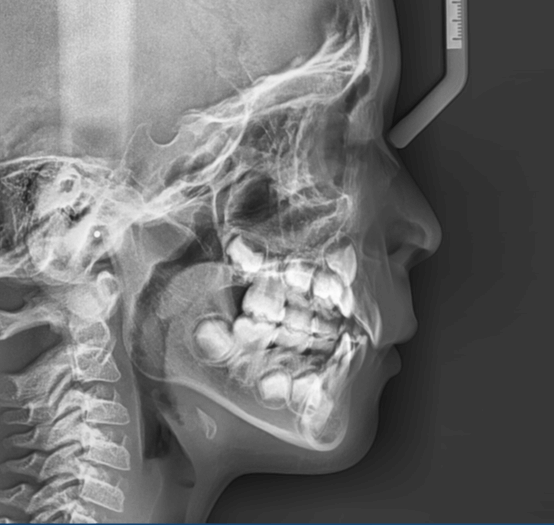

上歯前突+叢生症例 成長期

主訴 | 口元の突出感と歯並びが気になり、将来的な咬合状態を整える目的で来院された患者様です。 |

---|---|

診断結果 | 11歳1か月の女性。骨格的には日本人標準に近く、歯性の上顎前突および叢生が認められました。上下顎ともに歯列のスペース不足があり、永久歯の萌出や歯列の整列に支障をきたす可能性があると診断されました。 |

治療内容 |

|

治療後の経過 | 動的治療終了後は、上下顎の歯列が整い、口元の突出感と叢生が改善されました。審美的・機能的なバランスが取れた状態となり、現在は取り外し式リテーナーを使用し、保定期間に移行しています。 |

治療期間 | 動的治療期間:2年6か月 通院回数:25回 |

治療費用 | 720,000円 |